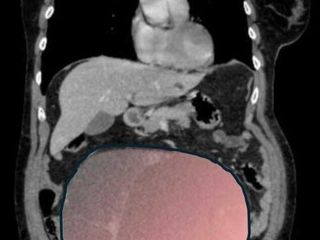

Il caso, definito dai medici un evento “normalmente eccezionale”, è stato preso in carico dalla Chirurgia Ginecologica mininvasiva dell’ospedale Sant’Anna di Torino, diretta dal dottor Paolo Petruzzelli. Nonostante le festività imminenti, la macchina della sanità piemontese si è attivata con una rapidità straordinaria: il 23 dicembre la paziente è stata sottoposta a un intervento durato sei ore che ha visto l’asportazione di una massa di ben 6 chilogrammi e un diametro di 28 centimetri.